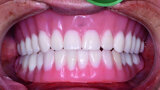

Fig. 22: Post-op retracted closedbite

view.